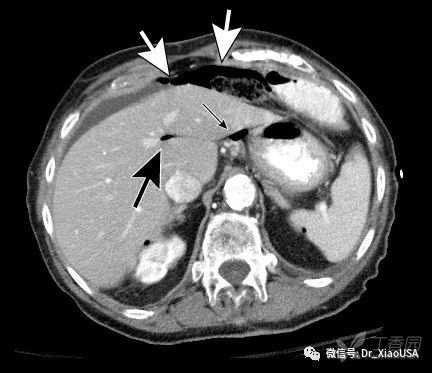

a) 腹腔内游离气体

a) 腹部CT